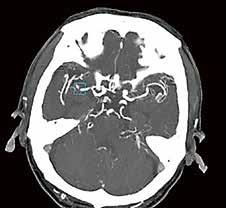

Gehirnblutung oder Gefäßverschluss

Handelt es sich um eine intrakranielle Blutung oder ist ein großes Gefäß verschlossen?

Ein Schlaganfall kann auf unterschiedliche Ursachen zurückzuführen sein. Deshalb ist es besonders wichtig, in kürzester Zeit über eine aussagekräftige Diagnostik zu verfügen.

Mit der Deep-Learning-basierten Auto-Stroke-Solution bringt Canon eine Lösung auf den Markt, die nicht nur selbstständig Bilder erstellt, sondern auch noch den Befundbericht dazu liefert.

Mit der Auto-Stroke-Solution präsentiert Canon eine Lösung, die in der Lage ist, ohne einen einzigen Klick unterschiedliche Arten von Schlaganfällen zu bestimmen und automatisiert eine detaillierte Auswertung zu erstellen. Um den Zustand des Schlaganfalls vollständig zu charakterisieren, analysiert das System, das auf Canons ebenfalls neuer Automation-Platform läuft, selbstständig CT-Scans. Den Notfallund Stroke-Teams werden in kürzester

Zeit Informationen zur Verfügung gestellt, die bei der klinischen Bewertung und Behandlung von Schlaganfällen helfen. „Die Auto-Stroke-Lösung integriert drei Schlaganfall-Applikationen, um sicherzustellen, dass die Untersuchung eine exakte Abbildung dessen liefert, was im Patienten vor sich geht“, beschreibt Michael Glasa, Produktmanager Healthcare IT und Manager Sales Support CT bei Canon Medical Systems, das neue System.

Diagnostik ohne Klick

Wenn die Zeit drängt, helfen die AutoStroke-Deep-Learning-Algorithmen bei Hirninfarktpatienten schnell, unterschiedliche Variationen einer intrakraniellen Blutung oder große Gefäßverschlüsse zu lokalisieren beziehungsweise die Penumbra und den potenziellen Infarktkern anzuzeigen. Denn die Kliniker benötigen schnellstmöglich Informationen, um in kurzer

Zeit fundierte Behandlungsentscheidungen treffen zu können. „Mit AutoStroke fassen wir nicht nur das Untersuchungsergebnis in einem Bericht zusammen, sondern stellen auch noch sicher, dass die Informationen ebenfalls auf mobilen Geräten, PCs oder im PACS eingesehen werden können“, erklärt Michael Glasa die Funktionsweise der Lösung für Schlaganfall-Netzwerke. Welche Therapie bei einem Schlaganfall die beste Option darstellt, hängt von vielen Faktoren ab. Speziell bei Verschlüssen großer Gefäße (LVO –Large Vessel Obstruction) scheint eine endovaskuläre Intervention im Vergleich zur systemischen Lyse bessere Ergebnisse zu liefern. Da im Falle einer Verlegung der Patient*innen eventuell Transportzeiten berücksichtigt werden müssen, ist eine möglichst exakte Diagnostik noch vor Ort von besonderem

Michael Glasa: „Eine schnelle Triage ist für den Patienten ausschlaggebend. Mit Auto-Stroke beschleunigen wir den gesamten Befundprozess. In weniger als 60 Sekunden analysieren die Algorithmen parallel die Bilder von bis zu drei unterschiedlichen Untersuchungen und die Befundberichte werden vollkommen automatisiert angefertigt, ohne dass eine Maus oder eine Tastatur bedient werden müssen.“

jedes einzelne Pixel. Die Software stellt sogar selbstständig fest, ob die Untersuchung mit oder ohne Kontrastmittel durchgeführt wurde.“ Handelt es sich um eine Untersuchung ohne Kontrastmittel, sucht Auto-Stroke nach einer Gehirnblutung und erkennt selbstständig die unterschiedlichen Arten: subdural, epidural oder subarachnoidal. Wurde bei der Untersuchung Kontrastmittel verwendet, sucht die Maschine nach einem Gefäßverschluss. Und auch Perfusionsstudien werden automatisiert ausgewertet. Sowohl die ausgewerteten Bilder als auch die maschinell erstellten Reports werden direkt ins PACS geschickt. Man kann das System auch so einstellen, dass es den Report per E-Mail entweder an die behandelnden Ärzt*innen oder zusätzlich an die Radiolog*innen versendet. Im PDF-

Hohe Sensitivität und Spezifität

Trotz der enormen Verlässlichkeit des Algorithmus liegt es an den weiterbehandelnden Ärzt*innen, das automatisiert erstellte Ergebnis zu validieren. Für die Analyse intrakranieller Blutungen wurde der Deep-LearningAlgorithmus anhand von mehr als 10.000 Fällen trainiert. Die gemessene Sensitivität beträgt 92 Prozent und die Spezifität erreicht einen Wert von 97,5 Prozent. Bei der Unterscheidung von Gefäßverschlüssen liegen die Werte von Sensitivität und Spezifität

bei jeweils 98 Prozent. Bei der CT-Perfusionsmessung nutzt die Anwendung die Bayesischen CTP+-Algorithmen, um die Penumbra und den Infarktkern ohne einen einzigen Klick zu quantifizieren. Dabei können nicht nur 2D-, sondern auch 4D-Studien gleichermaßen ausgewertet werden. Der große Vorteil von Auto-Stroke besteht darin, dass die Kliniker*innen innerhalb kürzester Zeit einen kompletten Befundbericht zugeschickt bekommen, um schnell die richtige Therapie-Entscheidung treffen zu können. Das System ist in der Lage, innerhalb eines Zeitraums von etwa 30 bis maximal 60 Sekunden automatisiert und mit hoher Zuverlässigkeit Schädel-CT-Scans auszuwerten und unterschiedliche Arten von Schlaganfällen zu differenzieren. //